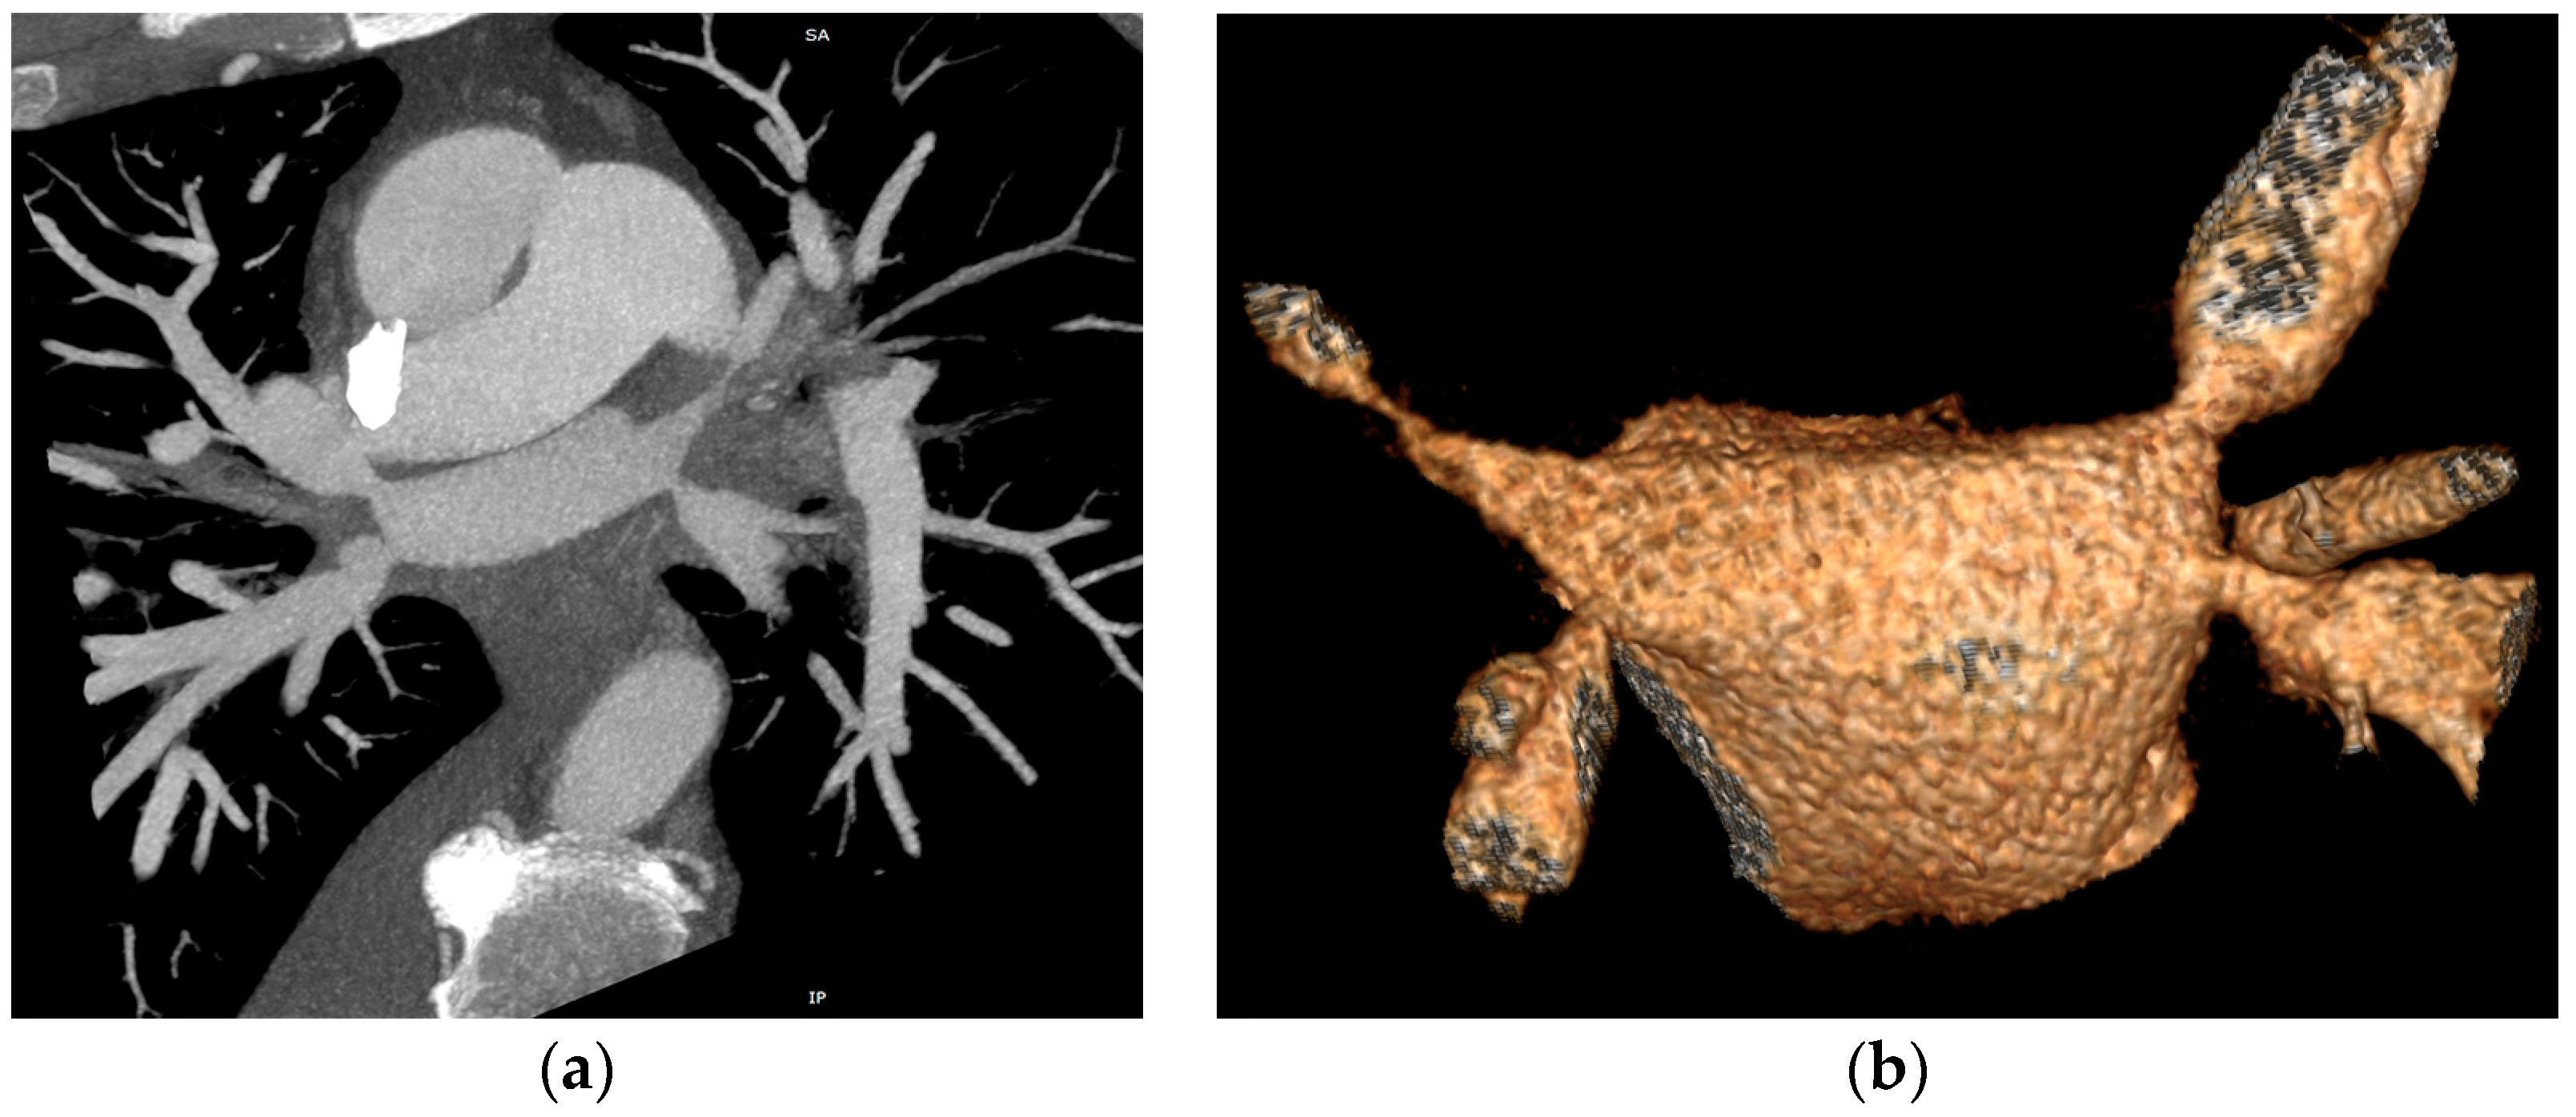

The CT study revealed stenosis of all four pulmonary veins (severe stenosis of the right superior, right inferior and left inferior PVs, near-occlusion of the left superior PV and of the vein draining the apical segment of the right lower lobe) (Figure 2).

Figure 2.

Cardiac CT angiography revealing stenosis of all four pulmonary veins: (a) maximum intensity projection (MIP) reconstruction; (b) volume rendering technique (VRT) reconstruction.